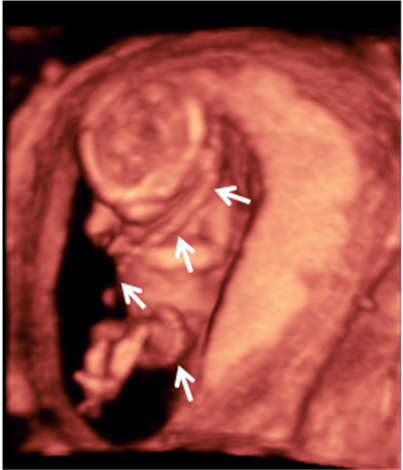

Ecografía Embarazo 4D Semana 12 - PRUEBAS DIAGNÓSTICAS